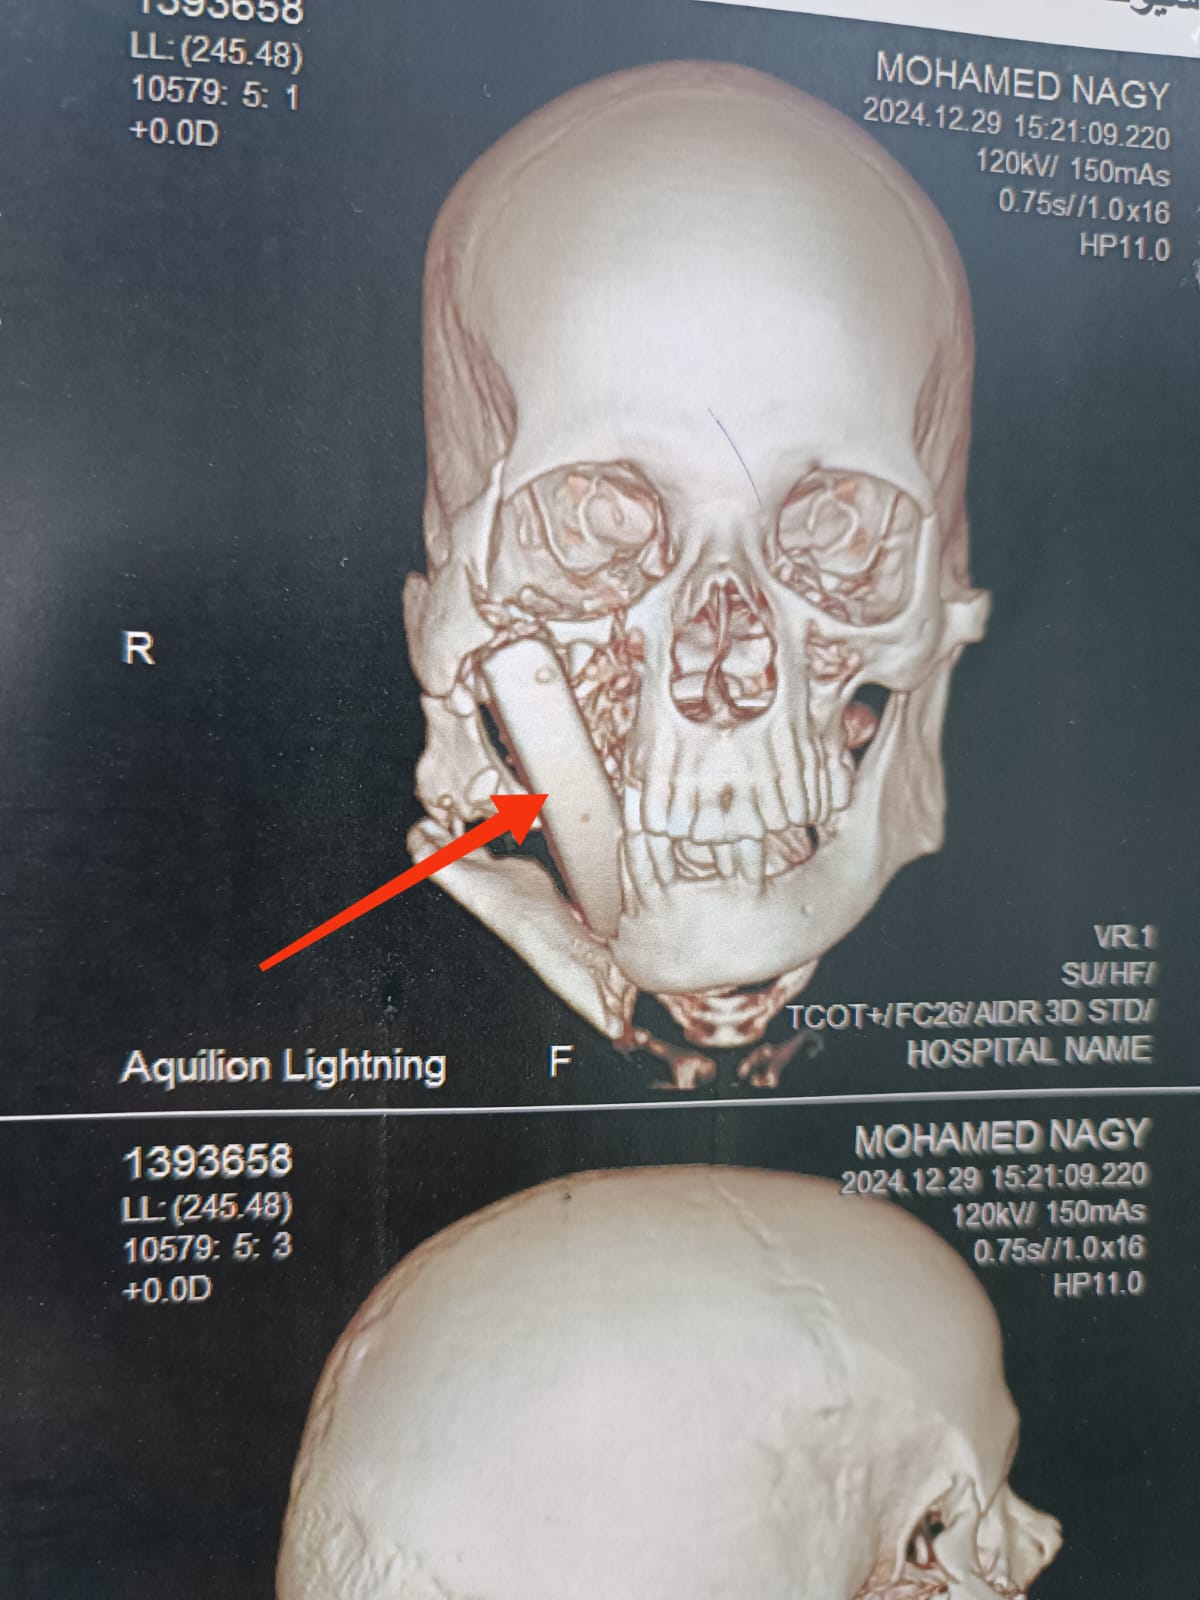

وكان مستشفي الإصابات الجامعي الجديد؛ استقبل مريضاً يبلغ من العمر ٥٠ عاماً، بعد تعرضه لإصابة بالغة أثناء أداء عمله بإحدى المناطق الحجرية، والذي نتج عنه تطاير قطعة حجرية كبيرة ارتطمت بوجه المصاب، وتسببت في حدوث تهتك بأنسجة الشفاه العلوية، واستقرت داخل أنسجة الخد الأيمن، مسببةً جروح بالغة؛ بالخد الأيمن، وقناة الغدة النكافية اليمنى، وسقف الحلق والبلعوم، كما تسبب فى كسور متعددة بعظام الوجنة اليمنى، والفك السفلى.

وتمكّن الفريق الطبي، بوحدة جراحات الوجه والفكين والرقبة؛ من تحضير المريض، والتدخل السريع؛ لإجراء جراحة عاجلة بعد عمل التجهيزات اللازمة، والإسعافات الأولية، ونجح الفريق في إصلاح أنسجة الخد، والفم، والبلعوم، مع استقرار الحالة الصحية للمريض بشكل جيد جداً، ويتم تجهيز المريض لمرحلة جراحية لاحقة؛ لتثبيت كسور الوجه.